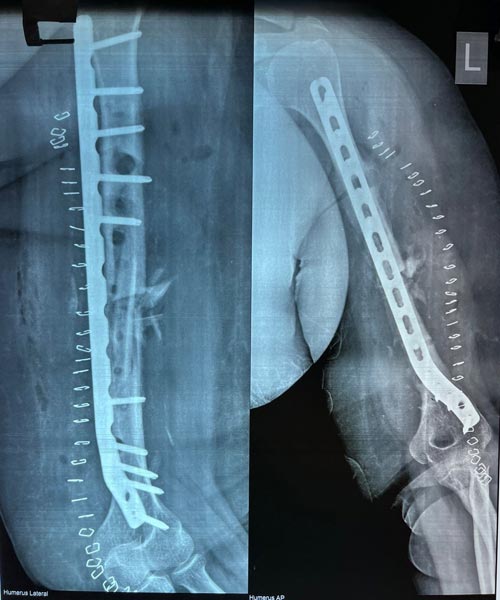

A bone fracture that is not currently healed and which will not even heal in the future is known as non-union. The non-union fractures are defined when there is no 9-month post occurrence or healing and has not shown any progress for three months.

Recovery and hospital stay at orthopedic hospital of a patient depends on the healing progress after orthopedic surgery which is determined by doctors by taking X-rays.

The treatment of non-union depends on the types of fracture and reasons for non-healing in the patient. In some cases, surgery is not required for the healing as they are treated with braces and various non-invasion methods.

In the surgeries, the surgeons mainly focus on